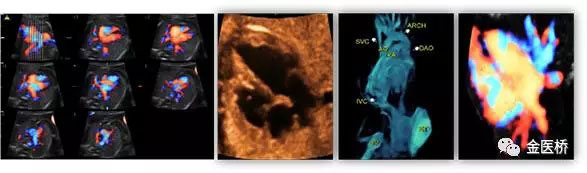

胎兒心臟超聲又名胎兒超聲心動(dòng)圖,是一種無創(chuàng)、安全的影像學(xué)檢查,也是胎兒期唯一有效的能夠顯示胎兒心臟結(jié)構(gòu)、血流及評估心臟功能的影像學(xué)手段,在產(chǎn)前及時(shí)診斷,隨診,預(yù)后判斷至關(guān)重要,不可替代。

一般情況下,一個(gè)詳細(xì)完整的胎兒心臟彩超檢查大約需要30-60分鐘。